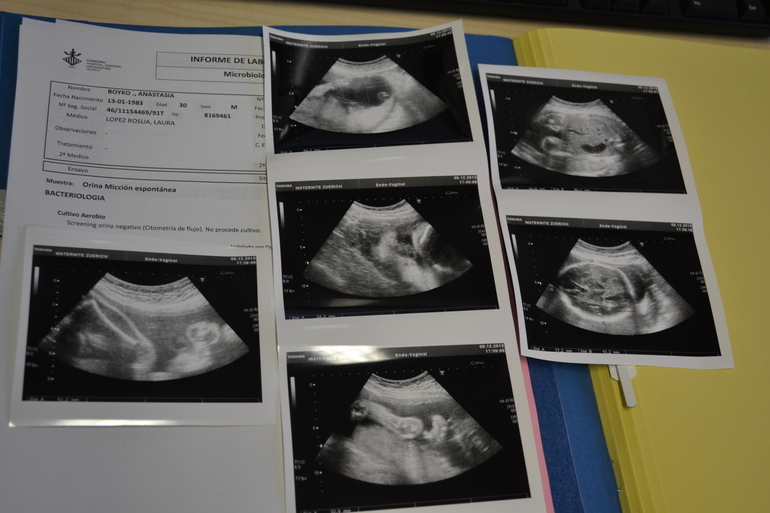

Наши недавние фото УЗИ

Пузяши наши, ВДМ, тазНаши УЗИ на 31н+6дн и фото пузика от 16+4 до 32+5

Лицо хорошо видно,черты лица кстати сильно отличаются от предыдущего УЗИ почему-то,на прошлом носик был такой маленький,а на этом очень большой,а у вас лицо после рождения отличалось от того что на УЗИ видно?

нам на каждом узи по многу фоток делают,но правда половину они себе забирают,но я тоже клянчу типа "ой,а можно еще и эту и вот эту"))))ну это правда зависит где делают,на 20-ой неделе мы в другом месте делали,так нам вообще ни одной не сделали даже...